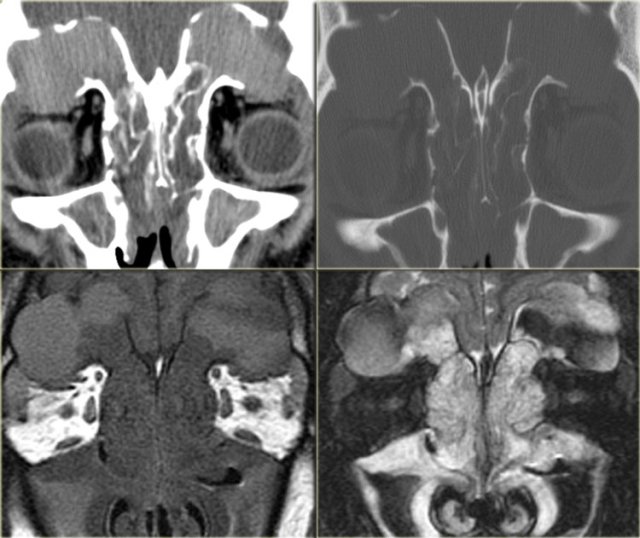

On the left CT-images of a patient post-lung transplant with fever and multiple rapidly progressing cranial nerve palsies.

We will show you CT- and MR-images of this patient. The diagnosis lymphoma was made through biopsy.

First study the images to study the extention od the disease.

On the CT-images the findings are:

• Soft tissue mass in the maxillary sinus (red arrow).

• Destruction of the sinus wall (yellow arrow).

• Remodelling and destruction of the pterygoid bone (blue arrow).

• Large soft tissue mass in the masticator space (asterisk).

The image on the right is more cranial.

There is opacification of the sphenoid sinus with destruction of and osteopenia of the sphenoid bone.

CT nicely demonstrates the bone destruction and some of the soft tissue involvement.

Continue with the MR-images.

On the left the corresponding MRI.

First study the images, then continue reading.

The findings are:

• Fluid in the right sphenoid sinus (red arrow).

• Hypointense tissue in the left sphenoid sinus (yellow arrows).

• Tracking along the dural margin of the middle cranial fossa (blue arrows).

• Extension into the left zygomatic-masticator space (large yellow arrow).

• Following contrast, there is no solid enhancement of the tissue in the sphenoid space.

Continue with the coronal images.

Coronal images of the same patient: T1 pre-and post-contrast.

Normal aspect of the right Meckel's cave, tissue in the left Meckel's cave extending into the cavernous sinus (blue arrow).

The red arrow points to the dural margin of the cavernous sinus: there is enhancement on both sides of the dura.

The disease wraps around the temporal lobe (green arrow) and extents downward in the foramen ovale (yellow arrow) and into the masticator space.

The asterix indicates normal non-enhancing tissue in the masticator space.

This patient had a lymphoma.

Nine out of ten times an immunocompromised patient will have a fungal infection, in one out of ten it will be a lymphoma.

CT and MR have a complimentary role in this case, but finally a biopsy is called for to differentiate between these two diagnoses, because of different treatment.